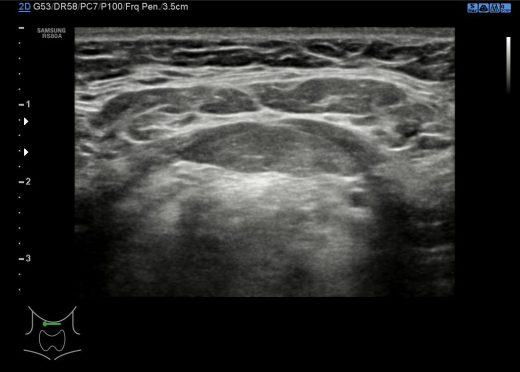

Cada región del cuello tiene que tener una foto en el estudio y que puedes ver a continuación, el objeto de esta división es la búsqueda de ganglios locorregionales, así como otros hallazgos extratiroideos que pudieran ser de interés, calcificaciones carotídeas, Tiroides ectópico, incluso las glándulas submaxilares (espacio 1 y 6 pegados al 4) y parótidas (espacio 1 y 6, debajo del pabellón auditivo u oreja).

Con esta división nos garantizamos que repasamos la parte lateral del cuello (1,2,3,6,7,8) y la parte central – superior al Tiroides (4) donde encontramos el Conducto del Tirogloso. También el espacio número 5 o escotadura supraesternal donde pueden ocultarse ganglios o restos del Timo.

Los espacios 1,2,3,6,7,8 siguen la longitud del Esternocleidomastoideo y todas las cadenas ganglionares del cuello.

Debemos permanecer muy atentos a la situación del pictograma y como se corresponde con los espacios del cuello de la foto superior.

En condiciones normales no tenemos que encontrarnos hallazgos patológicos, pero es habitual ver ganglios que no deben sobrepasar el centímetro de diámetro en eje corto para ser considerados normales, todos los hallazgos no normales deben ser registrados para posterior evaluación del Radiólogo/a.